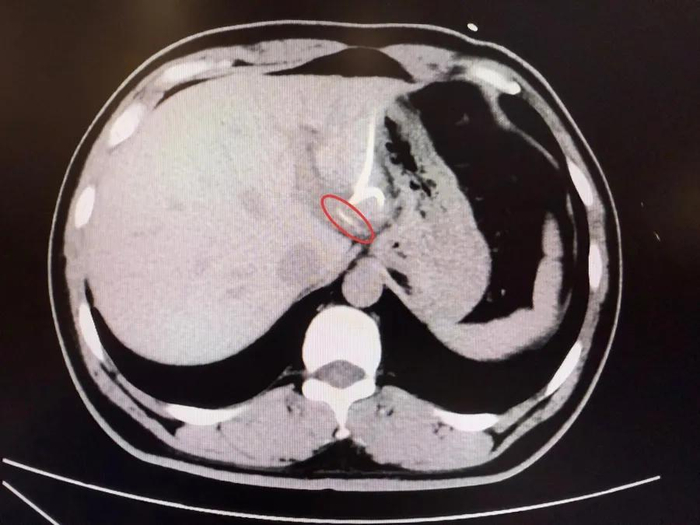

แพทย์จึงตัดสินใจทำการเอกซเรย์ CT Scan และพบสิ่งผิดปกติในตับซีกซ้าย มีก้อนแหลมยาวลักษณะคล้ายก้างปลาฝังอยู่ใกล้บริเวณกระเพาะอาหาร ตรวจสอบเพิ่มเติมพบว่า ก้างปลาดังกล่าวได้ทิ่มทะลุกระเพาะอาหารและแทงเข้าไปในเนื้อตับ ทำให้เกิดการติดเชื้อและเกิดฝีหนองขนาดใหญ่ภายใน

หลังผ่าตัดนานกว่า 3 ชั่วโมง แพทย์พบก้างปลาขนาดยาวประมาณ 3.5 เซนติเมตร แหลมคมเหมือนเข็ม ปักลึกอยู่ในเนื้อตับซีกซ้าย ทีมแพทย์สามารถนำออกได้สำเร็จโดยไม่ต้องตัดตับ หลังผ่าตัดผู้ป่วยอาการดีขึ้นอย่างต่อเนื่อง อุณหภูมิร่างกายกลับเป็นปกติ และฝีในตับค่อย ๆ ยุบลง